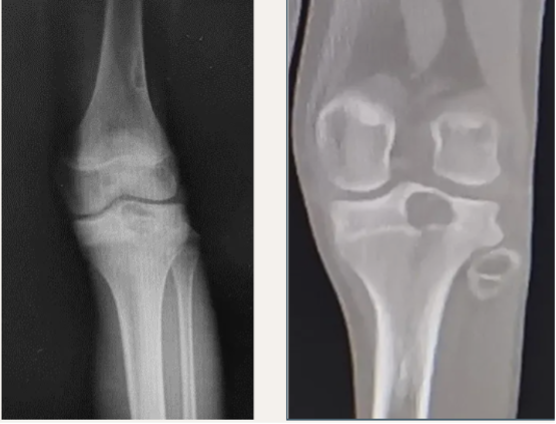

外院初诊影像:

读片:胫骨近端骨骺区密度不均匀透亮影,生长板以上地图样骨质破坏,直径约3cm,伴有薄层硬化边。磁共振上T1WI呈低或等信号,T2WI呈高低混杂不均匀信号,伴有骨髓水肿。